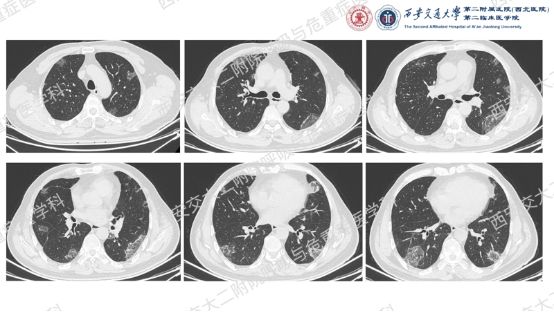

影像方寸藏玄机,同影异病辨真章。前几期我们一直在探索弥漫性囊性肺疾病的诊断,这一期我们切换到不同的影像模式,挖掘一下弥漫性肺部阴影的鉴别诊断。让我们继续乘风破浪,抽丝剥茧,解锁临床那些有意思的病例谜题吧!

结合以上病史及胸部CT,您的初步考虑?